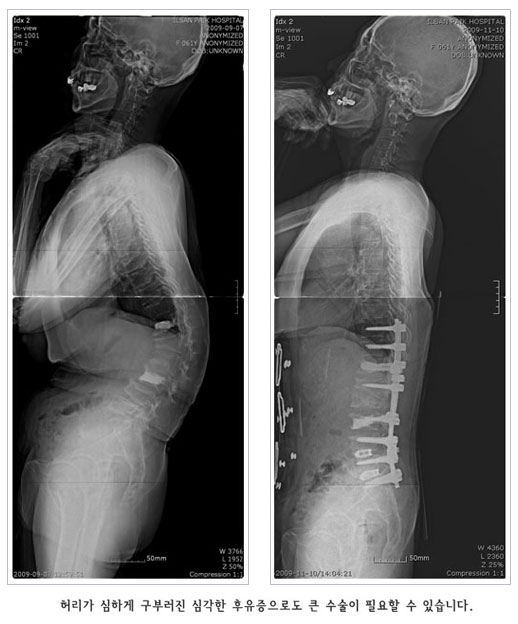

°ñ´Ù°øÁõÀº ¾à¹°Ä¡·á, ¿îµ¿ ¹× ½ÄÀÌ¿ä¹ýµîÀÇ º¸Á¸Àû Ä¡·á·Î ´ëºÎºÐ Àß ÇØ°áµÉ ¼ö ÀÖ½À´Ï´Ù. °ñÀýÀÌ »ý±ä °æ¿ì´Â ¾ÈÁ¤°ú º¸Á¶±â µîÀ¸·Î Ä¡·áÇÏÁö¸¸ ¼ö¼úÀû Ä¡·á°¡ ÇÊ¿äÇϱ⵵ ÇÕ´Ï´Ù. ôÃß°ñÀýÀÇ °æ¿ì¿¡´Â ÇǺÎÀý°³¸¦ ÇÏÁö¾Ê´Â ÃÖ¼Ò Ä§½ÀÀû ½Ã¼úÀÌ ÀÌ¿ëµË´Ï´Ù. ±×·¯¹Ç·Î Á¶±â¿¡ Ä¡·á ¹× ¿¹¹æÀ» öÀúÈ÷ ÇÏ´Â °ÍÀÌ Áß¿äÇÕ´Ï´Ù.

°æÇÇÀû ôÃß¼ºÇü¼ú (Vertebroplasty)

°ñ´Ù°øÁõ¼º ôÃ߾йڰñÀý¿¡¼­ ¼ö¼úºÎÀ§¸¦ ±¹¼Ò ¸¶ÃëÇÑ ÈÄ X-¼± Åõ½Ã±â·Î Åõ½ÃÇϸ鼭, °ñ ½Ã¸àÆ®¸¦ °ñÀýµÈ ºÎºÐ¿¡ ÁÖÀÔÇÏ¿© ôÃß»À ÀÚü¸¦ ưưÇÏ°Ô º¸°­½Ãŵ´Ï´Ù.

¡¤ ¿©·¯¹ø Àç¹ßµÉ ¼ö ÀÖÀ¸¹Ç·Î ƯÈ÷ ÁÖÀǸ¦ ¿äÇÕ´Ï´Ù.